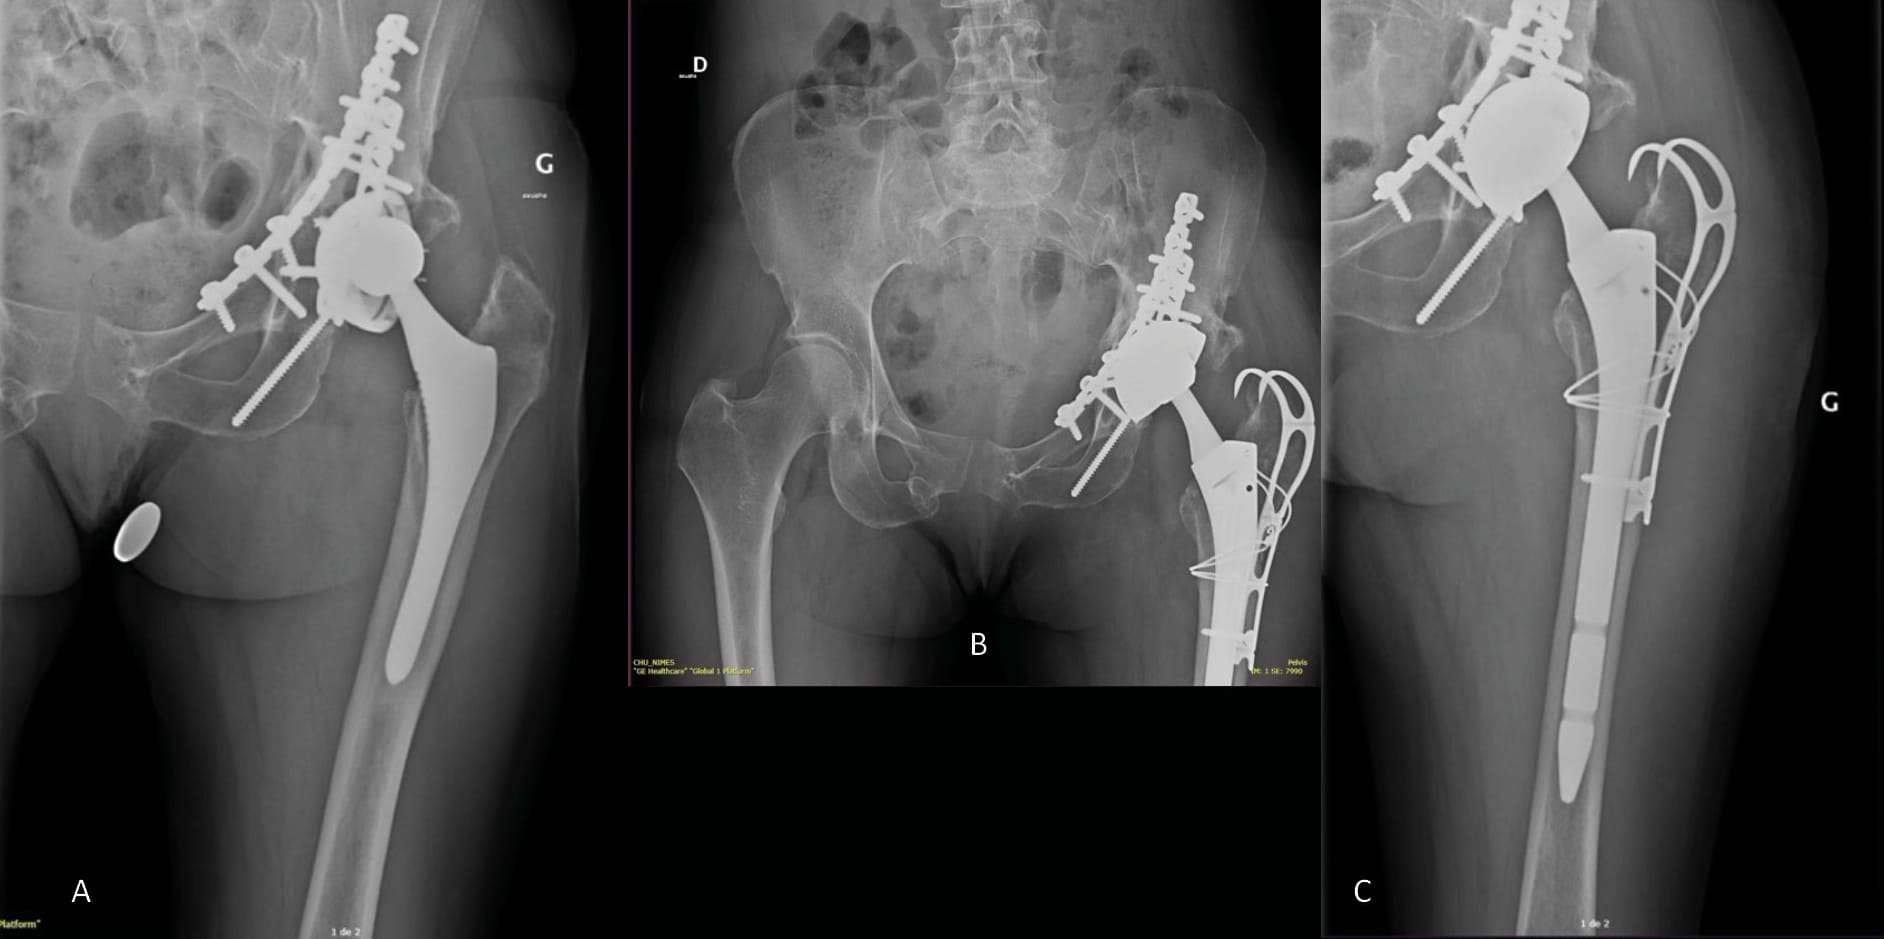

Nonetheless, bone reconstructions remain a surgical challenge, and all the more so when there is significant bone loss, the patient has undergone multiple operations and there is a context of chronic infection (Figure 8).

1. With bone-based biological reconstruction (Figure 7)

As part of a strategy that aims for bone reconstruction using a bone graft (autologous, allograft [54] Strahl A, Boese CK, Ries C, Hubert J, Beil FT, Rolvien T. Outcome of different reconstruction options using allografts in revision total hip arthroplasty for severe acetabular bone loss: a systematic review and meta-analysis. Arch Orthop Trauma Surg 2023. https://doi.org/10.1007/s00402-023-04843-9. or substitute [55] Romagnoli M, Casali M, Zaffagnini M, Cucurnia I, Raggi F, Reale D, et al. Tricalcium Phosphate as a Bone Substitute to Treat Massive Acetabular Bone Defects in Hip Revision Surgery: A Systematic Review and Initial Clinical Experience with 11 Cases. J Clin Med 2023;12:1820. https://doi.org/10.3390/jcm12051820.), indicated when there is moderate to significant loss of bone capital, it is often necessary to use an acetabular reinforcement device. Of the devices currently on the market, the Kerboull cross-plate is probably one of the most widely used in France and across Europe. As well as offering mechanical reinforcement, it also helps to restore the centre of rotation of the acetabular component and delivers primary stability that is adequate for subsequent integration of the bone graft. It requires precise positioning, which involves using the cross design as a guide to placement with the hook, centre and pallet in the vertical plane and the horizontal flanges in the horizontal plane, then the pallet should be in the horizontal plane parallel to the operating table. Achieving this final point sometimes requires a bone graft to be positioned between the pallet and the roof of the acetabulum [56] Assi C, Caton J, Aslanian T, Samaha C, Yammine K. The cross technique for the positioning of Kerboull plate in acetabular reconstruction surgery. SICOT-J 2018;4:20. https://doi.org/10.1051/sicotj/2018012.. If integrity of the U-figure (or pelvic tear drop, a bony ridge at the inferior medial acetabulum and overhanging the obturator foramen) is required to ensure stability, a structural graft to reconstruct this bony ridge is by default necessary [56] Assi C, Caton J, Aslanian T, Samaha C, Yammine K. The cross technique for the positioning of Kerboull plate in acetabular reconstruction surgery. SICOT-J 2018;4:20. https://doi.org/10.1051/sicotj/2018012.. Wegrzyn et al. carried out a study that aimed to evaluate the findings of a continuous and prospective case series of 61 revision THA with reconstruction of AAOS grade III and IV acetabular bone defects using a Kerboull cross-plate, structural allograft and cemented DM cup with a minimum follow-up of 5 years and a mean of 7.5 years. They reported no instability, and there was no failed acetabular reconstruction observed in 98% of the cases that presented complete osteointegration of the bone graft. Finally, no sign of mechanical rupture of the Kerboull cross-plate and/or loosening of the cemented cup were seen. As reported in other similar studies [19], Ciolli G, Mesnard G, Deroche E, Gunst S, Batailler C, Servien E, et al. Is Cemented Dual-Mobility Cup a Reliable Option in Primary and Revision Total Hip Arthroplasty: A Systematic Review. J Pers Med 2022;13:81. https://doi.org/10.3390/jpm13010081.[27], Assi C, Caton J, Fawaz W, Samaha C, Yammine K. Revision total hip arthroplasty with a Kerboull plate: comparative outcomes using standard versus dual mobility cups. Int Orthop 2019;43:2245–51. https://doi.org/10.1007/s00264-018-4209-z.[57] Bozon O, Dagneaux L, Sanchez T, Gaillard F, Hamoui M, Canovas F. Influence of dual-mobility acetabular implants on revision and survivorship of cup and Kerboull-type reinforcement ring constructs in aseptic acetabular loosening. Orthop Traumatol Surg Res OTSR 2022;108:103071. https://doi.org/10.1016/j.otsr.2021.103071., this reconstruction technique has produced excellent results at midpoint follow-up in terms of preventing instability after revision, restoring acetabular bone stock and stable cemented fixation of the dual mobility cup.